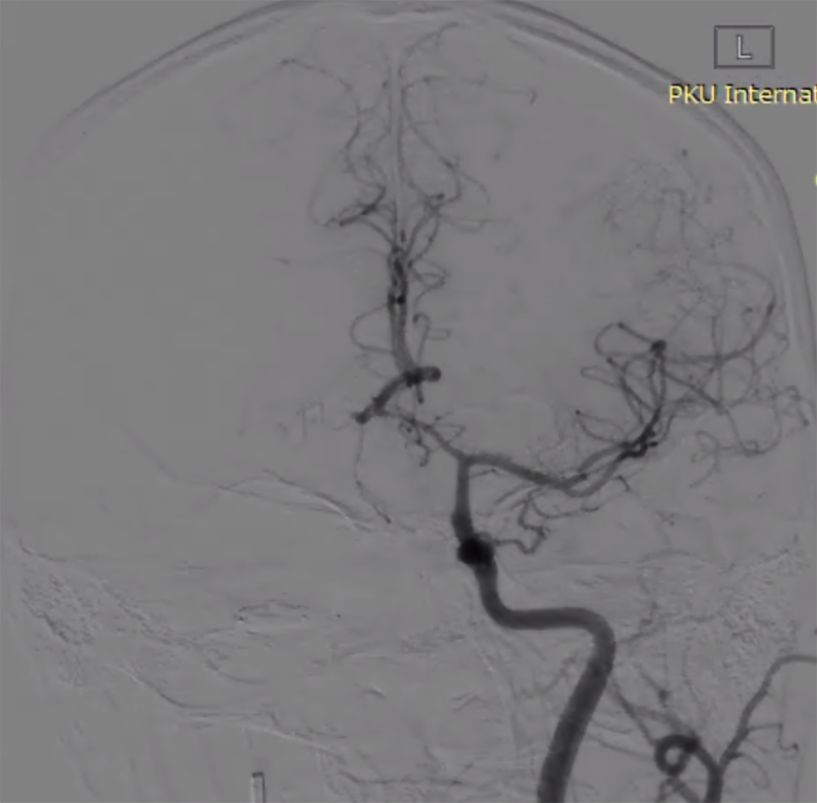

(2)左颈动脉造影见大脑前动脉抬高,右侧颈内动脉球囊闭塞试验见前交通动脉开放,M1段显影不良,考虑后交通供血较强(图2)。

图2

(3)后循环造影及右侧颈内动脉球囊闭塞试验,提示后交通供血较明显,可见动脉瘤显影,无法闭塞颈动脉,选择行动脉瘤栓塞术(图3)。

图3